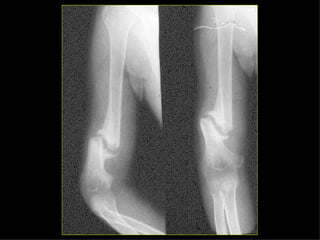

HOMBRO BRAZO CODO ANTEBRAZO MUÑECA MANO Monteggia Colles Fx escafoides

HOMBRO BRAZO CODOANTEBRAZO MUÑECA MANO Monteggia Colles Fx escafoides